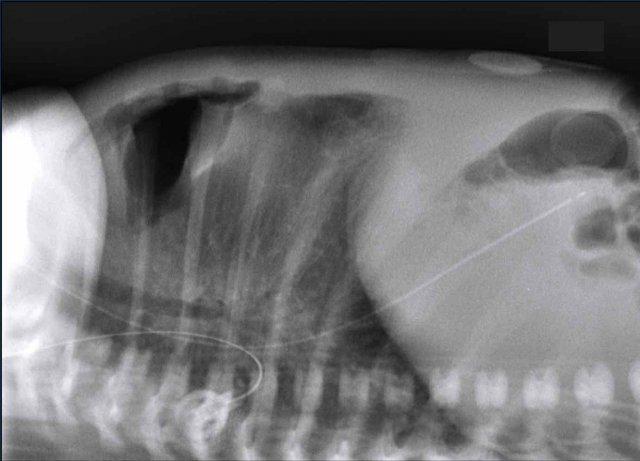

29 tuần + 1, ngày đầu tiên. CPAP.

Nhìn vào hình ảnh lần đầu.

Những phát hiện là gì?

Findings:

- Reticulogranular opacification

of lungs - Air bronchogram

- Consolidation in the right lower lobe

- Heart, vessels and

diaphragm are poorly defined. - Đặt sai vị trí catheter tĩnh mạch rốn (mũi tên), có thể nằm trong tĩnh mạch phổi.

- Nasogastric tube (NG tube) in good position.

Đây là trường hợp nặng của hội chứng suy hô hấp (RDS).

Chẩn đoán phân biệt bao gồm nhiễm trùng phổi do tình trạng đông đặc không đối xứng.